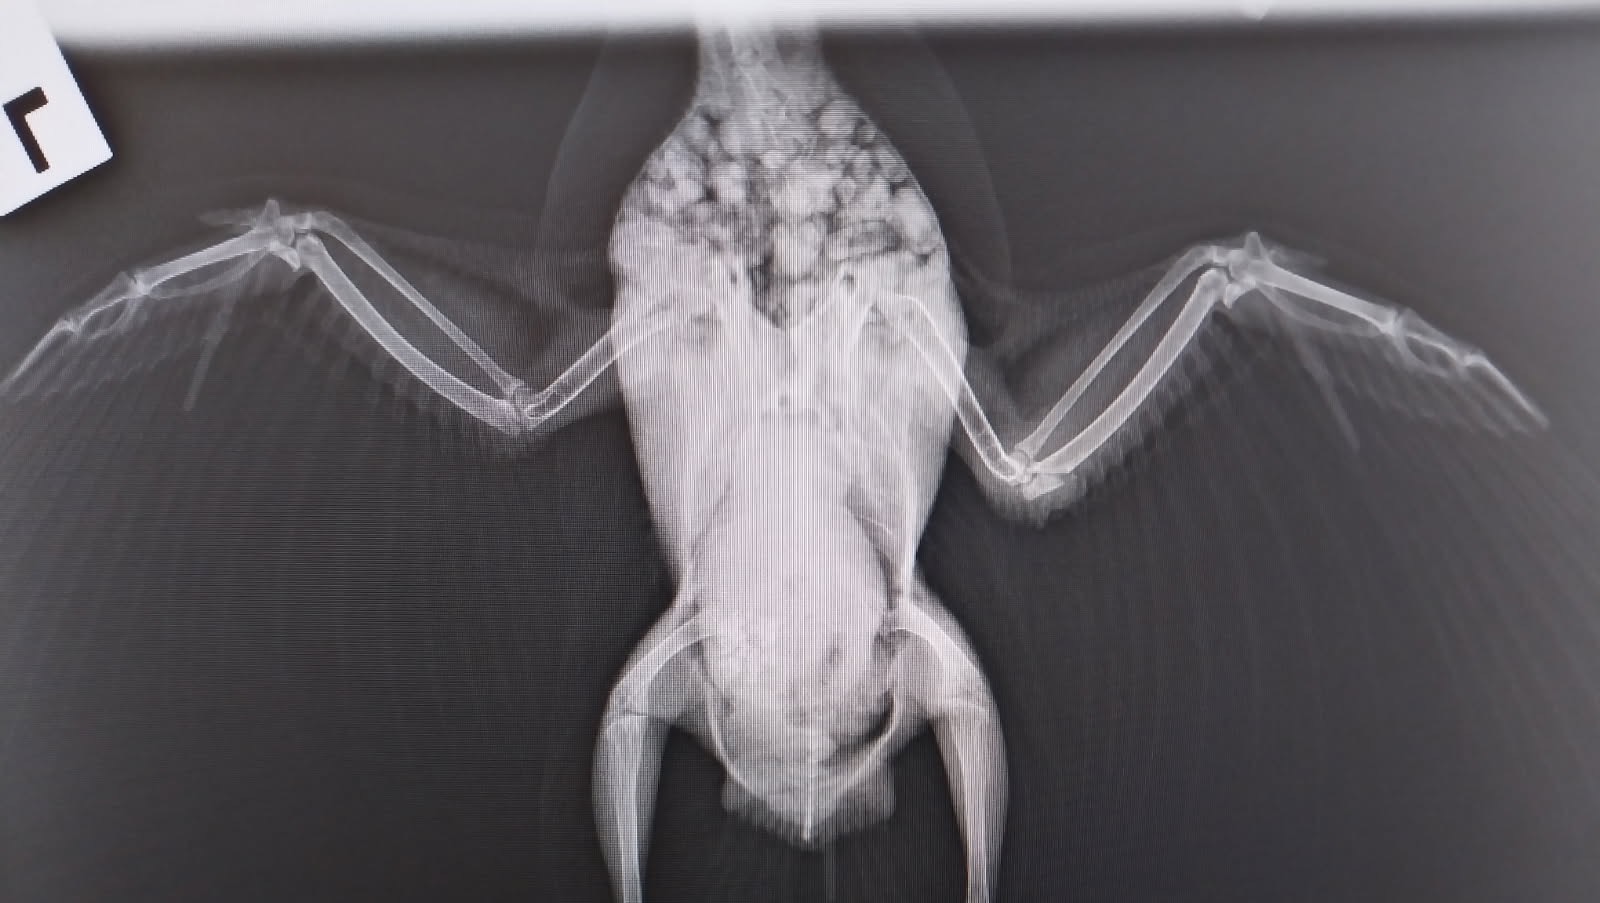

On the first day after her rescue, Margaret was terrified — she wouldn’t eat or drink, and just sat quietly in the corner. I knew she needed urgent help, so I took her to Dr. Nat at Campsie Vet. After an X-ray under anesthesia, we discovered her elbow was broken, most likely from a strong collision.

Margaret’s wing is now bandaged, and she receives medication twice a day. I’m keeping her movement minimal so the bone can heal properly. In two weeks, she’ll return for a follow-up check and, if recovery looks good, she’ll begin gentle physiotherapy to help her rebuild strength and, hopefully, fly again.